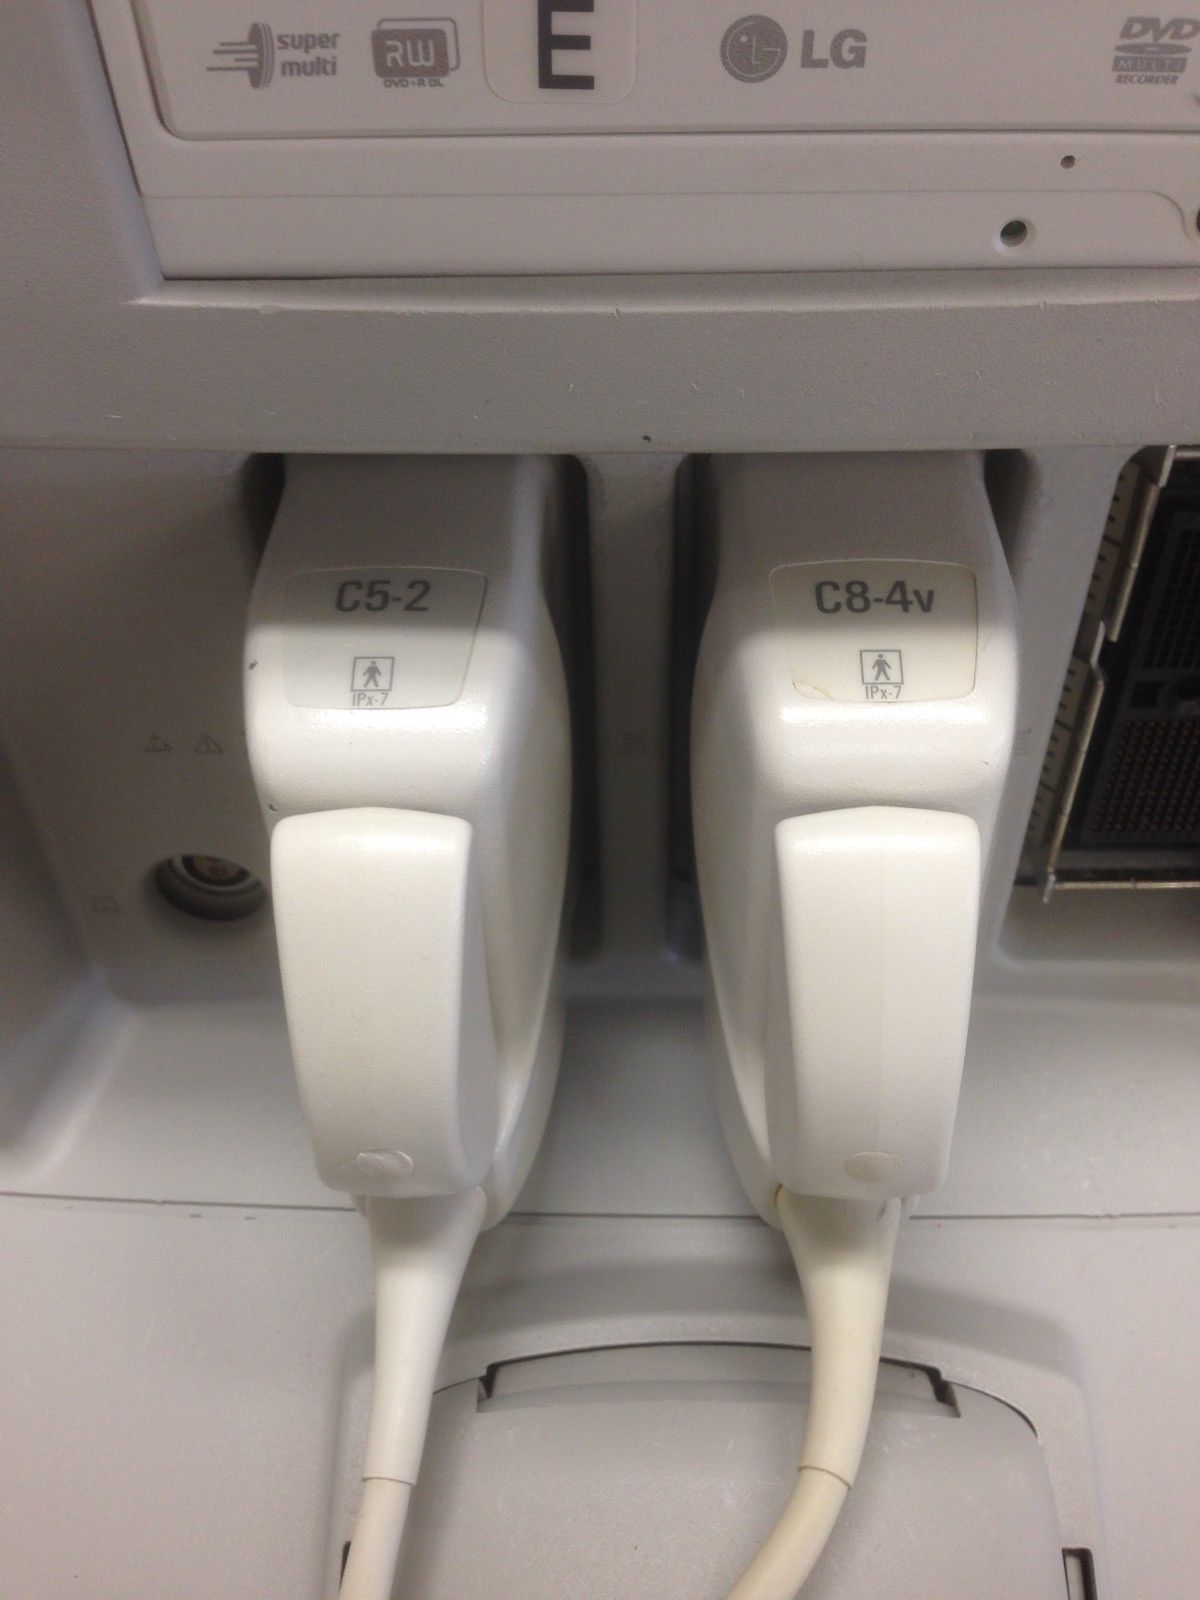

Philips Probes

DIAGNOSTIC ULTRASOUND MACHINES FOR SALE